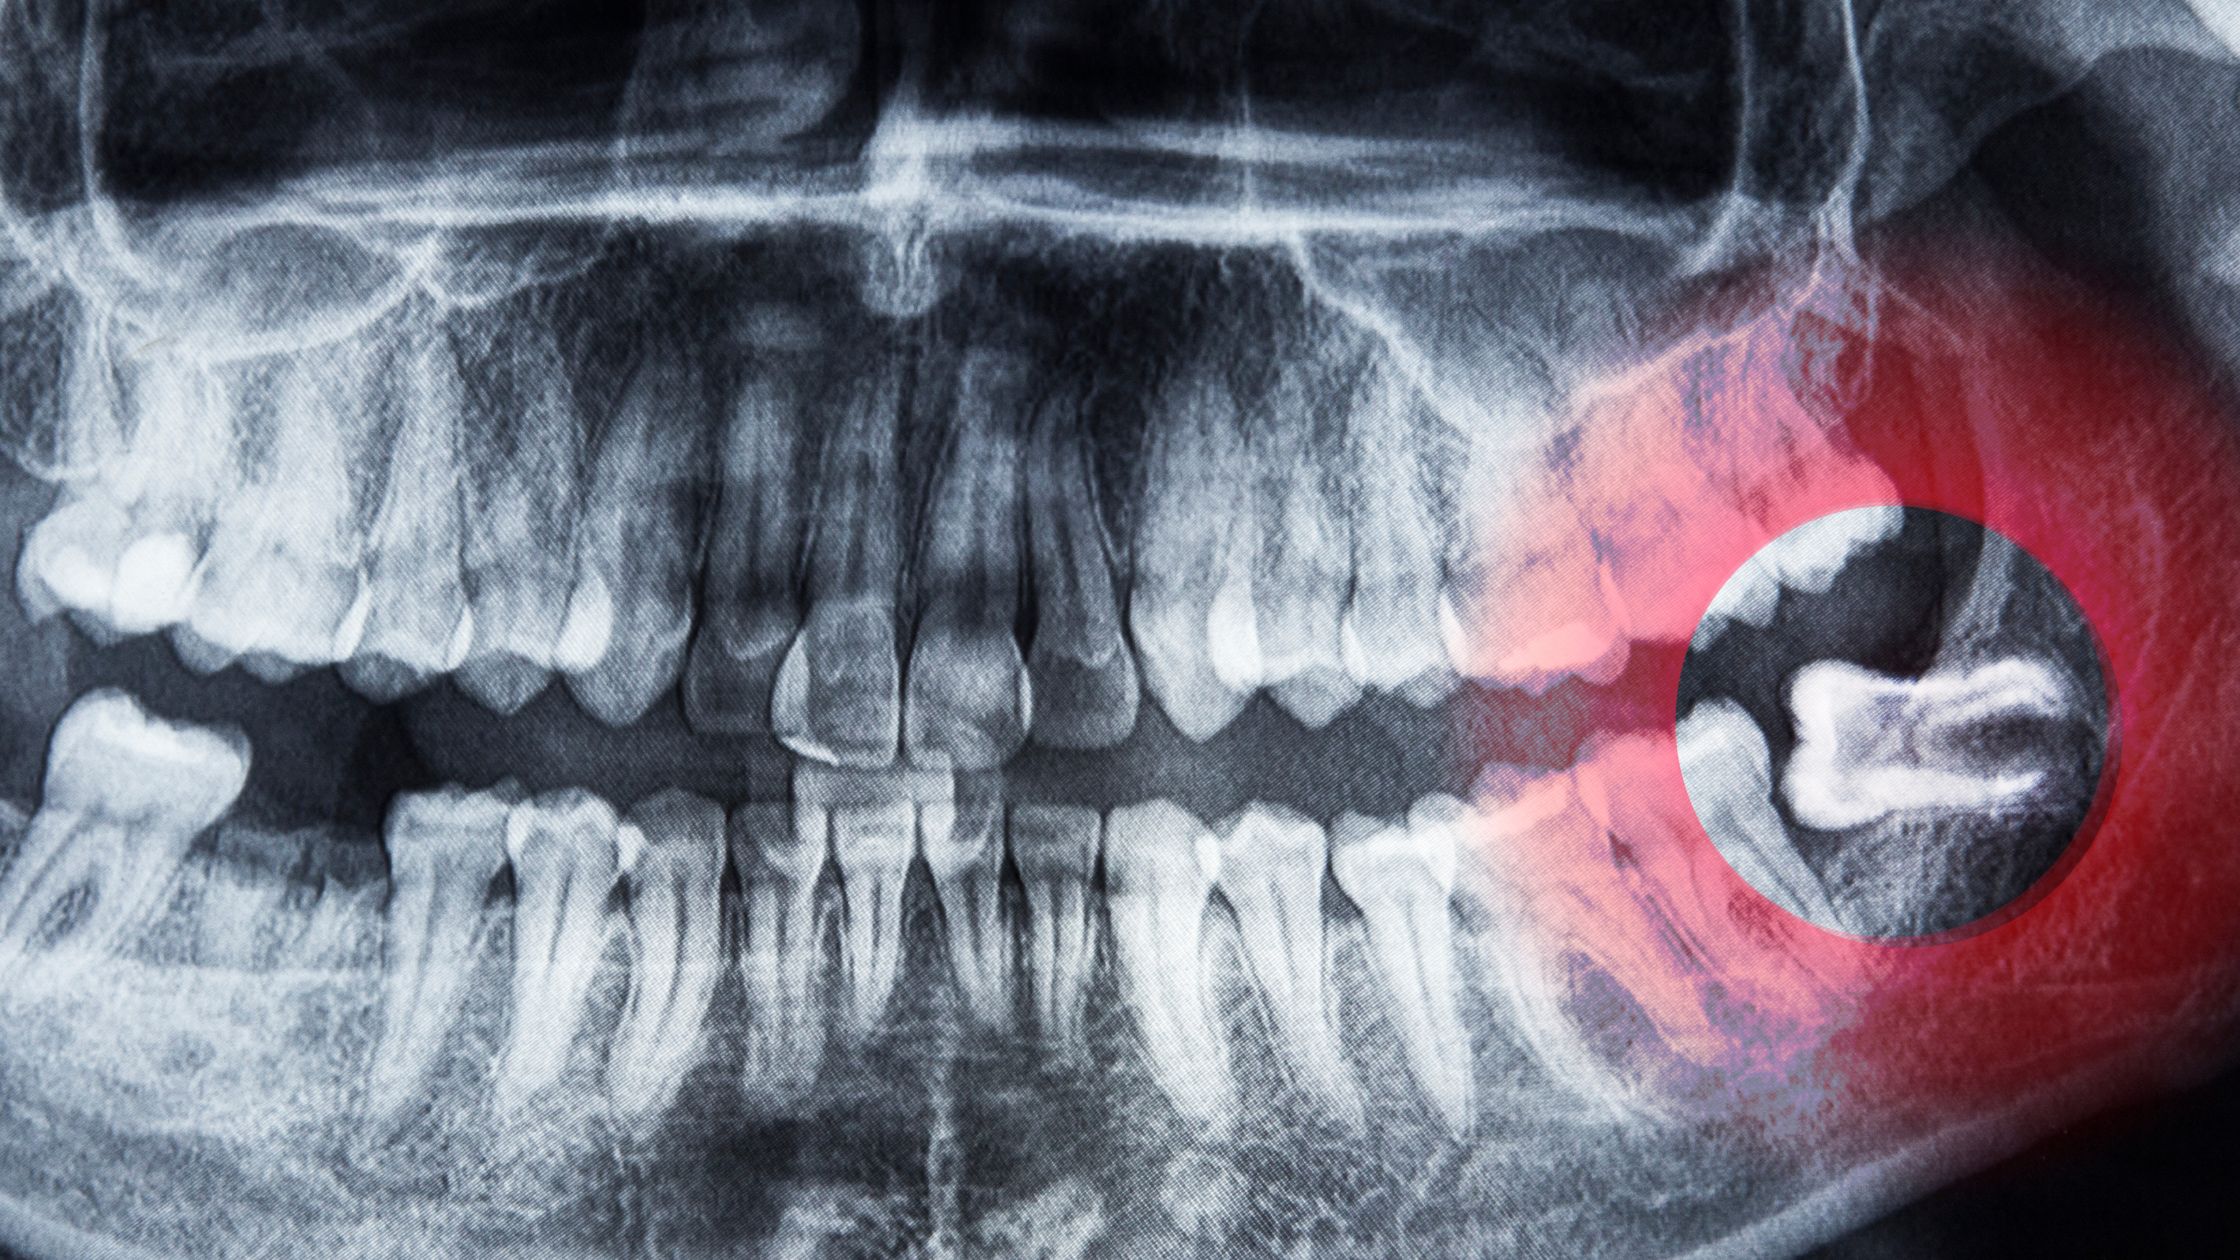

Un diente incluido es aquel que no ha erupcionado correctamente en su posición habitual dentro de la boca. En condiciones normales, los dientes erupcionan a través de las encías y se ubican en su posición final en la arcada dental. Sin embargo, en determinadas situaciones, un diente puede quedar atrapado y no ser capaz de emerger por completo.

Un diente incluido es un término utilizado en odontología para referirse a un diente que no erupcionado de manera adecuada en la cavidad oral. En lugar de ocupar su posición habitual en la hilera dental, queda atrapado bajo la encía o en el hueso maxilar, sin lograr emerger de forma normal. Esto puede ser resultado de varias causas, como la escasez de espacio en la boca, una incorrecta posición del diente, obstrucciones en su trayectoria de erupción, o incluso factores hereditarios.

Los dientes incluidos pueden ser tanto permanentes como temporales (dientes de leche). Los terceros morales, comúnmente conocidos como “muelas del juicio”, son un ejemplo típico de dientes incluidos. Cuando un diente permanente queda incluido, puede generar complicaciones como dolor, hinchazón, infecciones, maloclusión y otros problemas dentales.